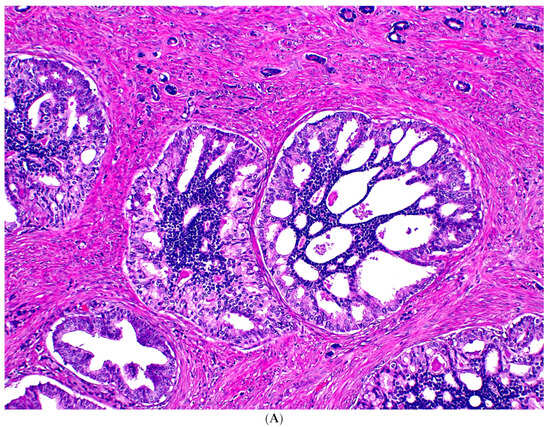

Although exceedingly rare, IDC-P has been observed in association with only GG1 PCa, distant from high-grade PCa, or even without a concurrent PCa (Figure 1) in rare RP specimens; and in these scenarios, IDC-P may represent a precursor lesion in prostate carcinogenesis rather than retrograde spread of high-grade PCa into pre-existing ducts and acini (see discussion below). IDC-P identified in these contexts have been reported in literature by various institutions [18,22,23,24,25,26,27,28], though some of these reports are not as convincing due to partial submission of RP specimens. A summary of the reported cases is provided in Supplementary Table S2.

Figure 1.

Isolated IDC-P without concomitant prostate cancer in a prostate biopsy (A,B). The IDC-P glands have residual basal cells positive for basal cell markers (brown stains) and are also positive for AMACR (red stain) (C). Isolated IDC-P is associated with unsampled GG ≥ 2 PCa in the majority of cases, although no invasive or only GG1 PCa is found in subsequent RPs in approximately 10% of cases.